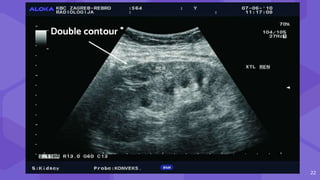

● Double contour

● Compression of renal collecting

system, vascular pedicle

Small subcapsular hematoma.

Double contour